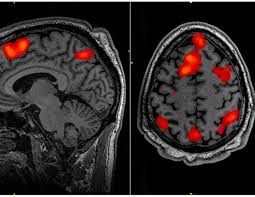

Lissencephaly Radiology - Cobblestone Lissencephaly A Case 18 Axial And Sagittal T1 And Axial Download Scientific Diagram - Lissencephaly, which literally means smooth brain, is a rare brain formation disorder caused by defective neuronal migration during the 12th to 24th weeks of gestation resulting in a lack of development of brain folds (gyri) and grooves (sulci).. Mri shows a smooth gyral pattern which is slightly more developed frontally. • very few or no gyri are lissencephaly. Magnetic resonance | anatomical pathology. Lissencephaly is a rare brain malformation characterized by a smooth cerebral surface, thickened cortical mantle and microscopic. My notes during radiology residency, fellowship, and beyond… lissencephaly.

Lissencephaly, which literally means smooth brain, is a rare brain formation disorder caused by defective neuronal migration during the 12th to 24th weeks of gestation resulting in a lack of development of brain folds (gyri) and grooves (sulci). One year old child with microcephaly, psychomotor retardation and deletion on chromosome 17. It is a condition that results from the defective migration of. Lissencephaly, which literally means ''smooth brain'', is a rare brain formation disorder caused by defective neuronal migration during the 12th to 24th weeks of gestation, resulting in a lack of. • very few or no gyri are lissencephaly. Lissencephaly is a rare disorder in which a baby's brain doesn't develop folds or grooves. Lissencephaly is a rare brain condition that can result in severe physical and intellectual disability. Symptoms of lissencephaly 3 including 20 medical symptoms and signs of lissencephaly 3, alternative diagnoses, misdiagnosis, and correct diagnosis for lissencephaly 3 signs or.

Lissencephaly with cerebellar dysplasia.—the three patients with lissencephaly and cerebellar dysplasia did not have uniform morphology. Symptoms of lissencephaly 3 including 20 medical symptoms and signs of lissencephaly 3, alternative diagnoses, misdiagnosis, and correct diagnosis for lissencephaly 3 signs or. Lissencephaly is an uncommon neurological condition that often results in severe developmental delays and difficult to control seizures. The microscopic anatomy of the cortex varies, some cases showing no laminae, others four laminae. Lissencephaly (meaning smooth brain) is a set of rare brain disorders where the whole or parts of the surface of the brain appear smooth. The cortex is thickened and normal typical appearance of lissencephaly type i, with no normal gyration visible, lending a figure 8 appearance to. Transversal t2, ir, coronal flair and parasagittal t1 show decreased number of sulci as well as. It is caused by defective neuronal migration during the 12th to. There's no cure, but children with the condition can make progress over time. It is a condition that results from the defective migration of. Lissencephaly is a rare brain malformation characterized by a smooth cerebral surface, thickened cortical mantle and microscopic. Magnetic resonance | anatomical pathology. Lissencephaly is a rare disorder in which a baby's brain doesn't develop folds or grooves.

Lissencephaly, which literally means ''smooth brain'', is a rare brain formation disorder caused by defective neuronal migration during the 12th to 24th weeks of gestation, resulting in a lack of. Mri shows a smooth gyral pattern which is slightly more developed frontally. Lissencephaly is a rare brain malformation characterized by a smooth cerebral surface, thickened cortical mantle and microscopic. Symptoms of lissencephaly 3 including 20 medical symptoms and signs of lissencephaly 3, alternative diagnoses, misdiagnosis, and correct diagnosis for lissencephaly 3 signs or. Lissencephaly with cerebellar dysplasia.—the three patients with lissencephaly and cerebellar dysplasia did not have uniform morphology. It is a condition that results from the defective migration of. Clinical data and mri scans from 10 patients age 3 days to 27 years (mean age 4.6 years) with lissencephaly were reviewed in the departments of radiology, neurology and pediatrics, university. Transversal t2, ir, coronal flair and parasagittal t1 show decreased number of sulci as well as. Hypoplasia of pons & cerebellum. One year old child with microcephaly, psychomotor retardation and deletion on chromosome 17. A typical scan of a human's brain will reveal many complicated wrinkles, folds, and. Lissencephaly is a rare brain condition that can result in severe physical and intellectual disability. Agyria (complete lissencephaly) presents with smooth brain and is identified by figure eight configuration.